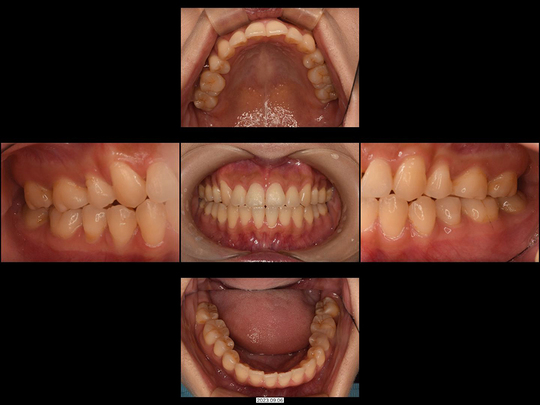

Kさん 40代 女性

矯正前

画像をクリックで拡大

矯正後

左上の前歯1本が反対咬合になっているのが気になっておられました。改善するには、そこの歯を抜いてブリッジにするしかないという診断を受けたことがあるそうです。しかしカウンセリング時に細かくお話を伺ったところ「抜いたり削ったりしたくない、今よりも磨きやすくなりたい。右の古い前歯の色が変わっているのも気になる」とのことでした。

右上の前歯は歯ぐきの色が黒くなっていました(メタルタトゥー)ので、矯正治療前に古い金属の土台を撤去。「プロビジョナルレストレーション」とよばれる自費診療の仮歯を使用して、左側の反対咬合の歯を動かす際のスペースを確保。歯の移動中に、メタルタトゥーによる黒ずんだ歯ぐきをレーザーにて対応しました。ご了承のもと、右上前歯はセラミック治療を行っています。非抜歯、上だけの部分矯正です。

治療の期間・回数

12か月、15回

​費用

614,000円